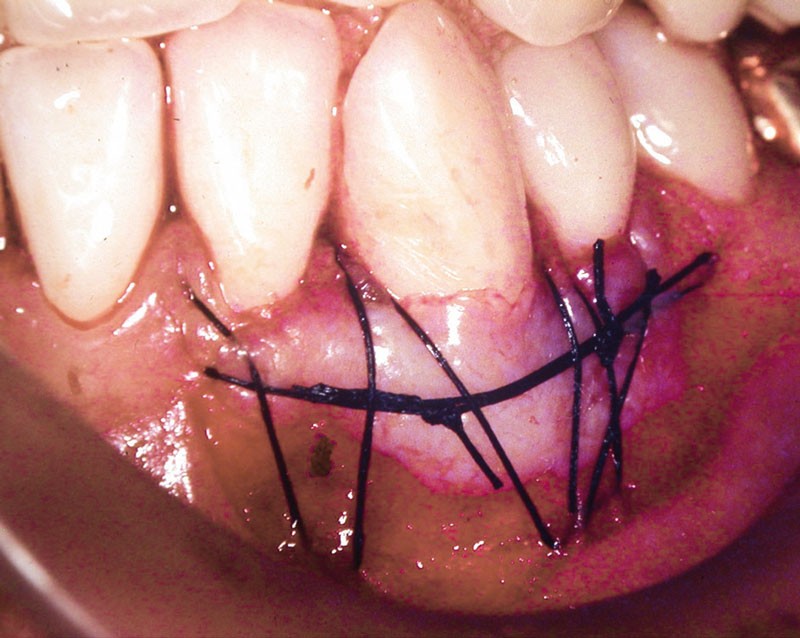

Dans ce deuxième cas, la canine mandibulaire présente également une absence de gencive attachée, associée ici à une récession gingivale (fig. 3).

Une greffe épithélio-conjonctive est réalisée (fig. 4).